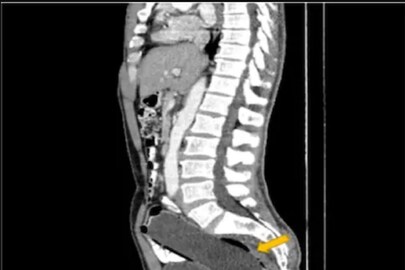

ব্যথায় কাতরাতে থাকেন ওই ব্যক্তি। অবশেষে ওই ব্যক্তির স্ত্রী তাকে নিয়ে ডাক্তারের কাছে যান। ডাক্তার সবটা শুনে সিটিস্ক্যান করার পরামর্শ দেন। এবং ব্যক্তিকে সঙ্গে সঙ্গে হাসপাতালে ভর্তি করে নেন। এর পর ওই ব্যক্তির তলপেট, রেকটাম স্ক্যান করা হয়। স্ক্যানের রিপোর্ট দেখে মাথায় হাত সকলের। চমকে যান ডাক্তার নিজেও। বুঝে পাচ্ছিলেন এ কী করে সম্ভব! যা জানলে আপনিও অবাক হবেন বইকি! ওই ব্যক্তির রেকটামে ঢুকে রয়েছে এক অদ্ভুত জিনিস। কিন্তু কি করে সম্ভব? তা নিয়ে প্রশ্ন থাকলেও, সামাধান হয়।

সিটি স্ক্যানে জানা যায় ওই ব্যক্তির রেকটানে সাত ইঞ্চির একটি জলের বোতল ঢুকে রয়েছে। আর এই বোতল থেকেই অসহ্য ব্যথা হচ্ছে তার। সময় নষ্ট না করে অপারেশন করার সিদ্ধান্ত নেন ডাক্তাররা। খুব সতর্ক ভাবে বের করে আনা হয় সেই বোতল! পাঁচ দিন পর তাকে হাসপাতাল থেকে ছেড়েও দেওয়া হয়। কিন্তু রেকটামে বোতল কী ভাবে এল তা নিয়ে চাঞ্চল্য তৈরি হয়। অবাক হন ডাক্তার এবং ওই ব্যক্তির স্ত্রী! জানা যায় ওই ৫০ বছরের ব্যক্তি বিকৃত কামের শিকার! যৌন উত্তেজনা পেতে নিজেই ওই বোতল রেকটামে ঢুকিয়ে দেন ব্যক্তি। ভেবেছিলেন বেরিয়ে যাবে নিজে থেকে। কিন্তু তা হয় না! ভয়ে ওই ব্যক্তি কাউকে কিছু বলতে পারছিলেন না। তবে খবর জানাজানি হতেই ভাইরাল হয়।